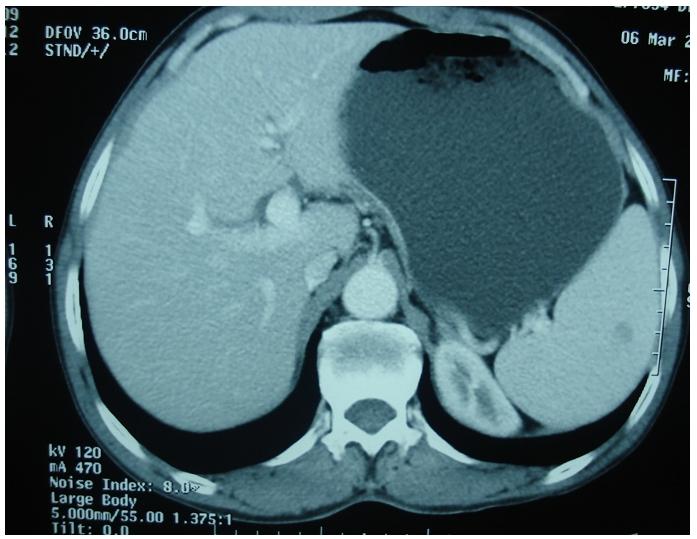

El M'rabet Fatima Zahra, Brahmi Sami Aziz, Rachidi Siham, Tizniti Siham, Amaarti Afaf, Ait Taleb Khalid, El Mesbahi Omar

Service d'Oncologie Médicale, CHU Hassan II, Fès, Maroc.

Pan Afr Med J. 2011;10:44. Epub 2011 Nov 23.